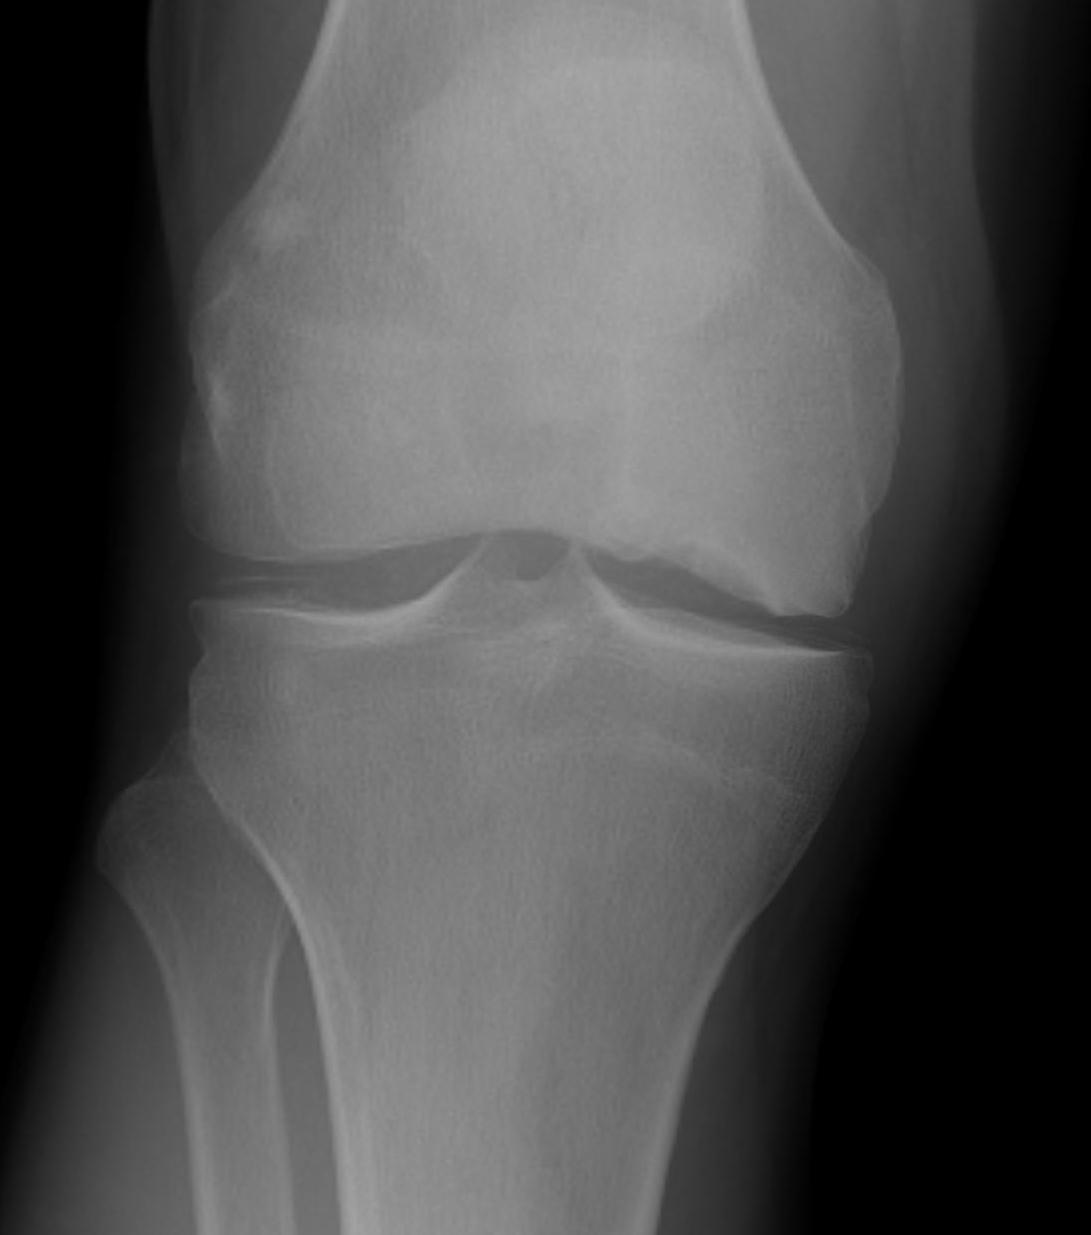

X-ray

Initially normal

Later develop

- subchondral lucent line / crescent Sign

- flattening of condyle

- patchy sclerosis

- can have rapid collapse into varus with development degenerative changes